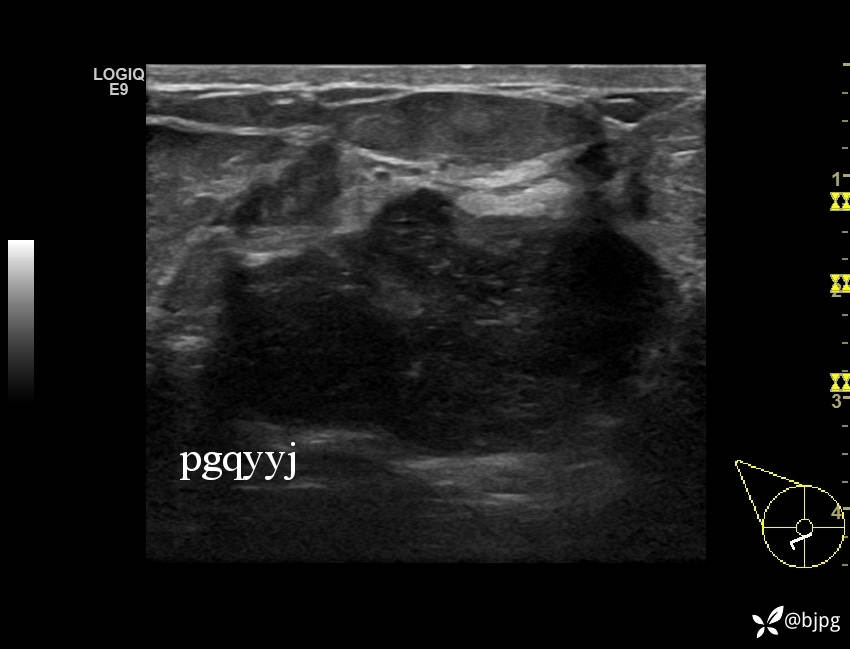

【患者信息】:女性36岁

【主诉】:发现右乳肿物一周

【检查】:超声

【临床诊断】:右乳结节,性质待定

【治疗经过及结果】:穿刺活检,欢迎同道讨论,穿刺病理数日后公布。

乳腺分叶状肿瘤 (7)